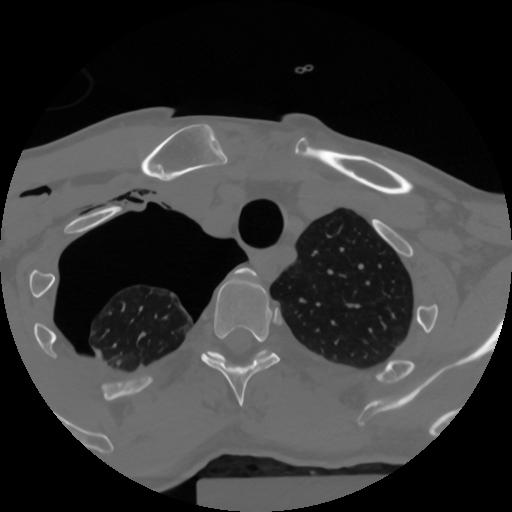

12 P.BLANDAS,,Vol,0.5,P.BLANDAS,,